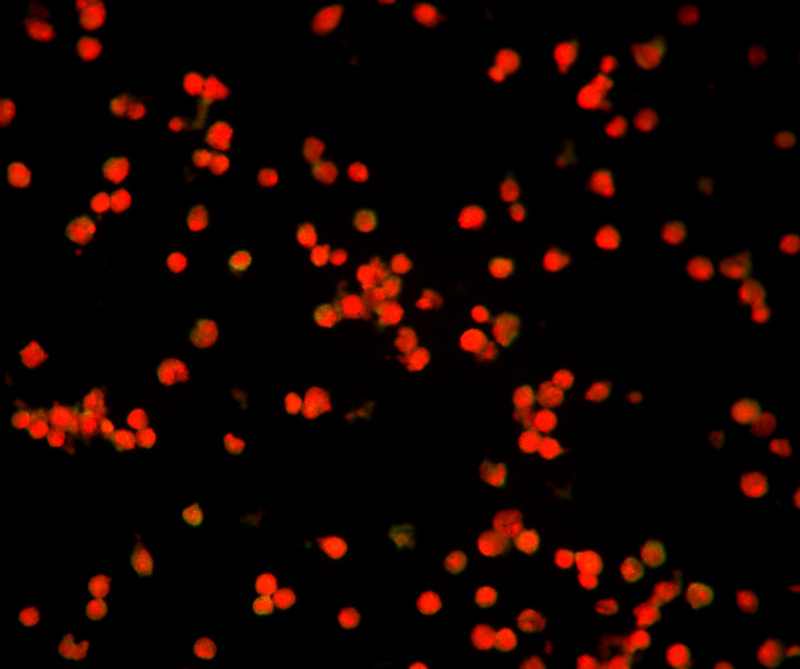

流感疫苗_06.jpg

流感病毒检测阴性

使用荧光显微镜400倍视野观察(40X物镜),甲型流感检测孔位荧光少且弱,视为阴性结果,荧光亮度强数量多,平均每个视野的阳性细胞大于3-5个,就可以判断为阳性。乙型流感另有一个孔位,判断标准和甲型流感一致。

流感疫苗_07.jpg

流感病毒检测阳性

免疫荧光法检测快速,而且准确性高于胶金体法,因此得到越来越多医疗机构的选择。